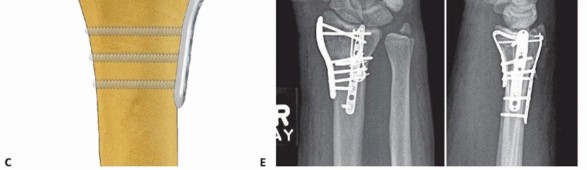

TECH FIG 8 • Radial column fixation with radial pin plate. A. Insertion of trans-styloid Kirschner wire. B,C.

TECH FIG 9 • Radial column fixation with fixed-angle radial column plate. A. Provisional placement of fixed-angle radial column plate. B. Drilling holes for distal fixed-angled pegs. C. Completed fixation. D. Unstable fracture injury films with segmental radial column comminution. E. Films 2 months postoperatively. Fixed-angle radial column support is used to avoid radial column shortening. Using fixed-angle drill guides, drill, measure, and insert locking fixation pegs of appropriate length into the distal fixed-angle holes in the plate and standard bone screws proximally into the shaft ( TECH FIG 9B-E).P.2873. Ulnar Corner and Dorsal Wall Fixation